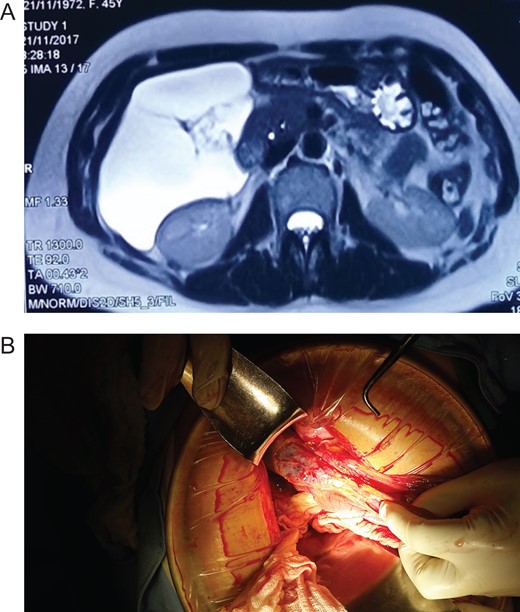

Patient is a 45-year-old female patient, with past medical history of gastritis. Six months before she sought medical attention, she was complaining of mild upper abdominal pain, however, due to her previous condition she was medicated with proton pump inhibitors assuming that the pain was due to her gastritis. In the last 3 months, she noticed a mass in her upper abdomen and the pain became more severe and started to affect her daily activities, thus she presented to a routine physical exam. No weight loss or other constitutional symptoms were noticed. Also no history of malignancy in her family was mentioned. On clinical examination, a 12 × 15 cm2 mass was discovered on her upper abdomen, mild pain was found on palpation but no tenderness was present. An abdominal ultrasonography revealed a 15 × 15 cm2 septate thin-walled giant cystic mass, it was anechoic and had a volume of ~735 ml. The cyst occupied most of the hepatorenal space and it was in intimate contact with the liver, right kidney and pancreas (Fig. 1A). Due to the size of the mass, CT was requested, it revealed well-defined 19.7 × 15 × 10 cm3 giant cyst, the cyst was located within the small bowel mesentery and it was in intimate contact with the liver, gallbladder, pancreas and right kidney (Fig. 2A). Nevertheless, the tomography could not rule out that the mass had some sort of communication with the bile duct or the pancreas. This is why a magnetic resonance cholangiopancreatography found that the cyst was attached but had no communication with the bile duct or the pancreas (Fig. 3A). CBC and blood work was normal.

(A) MRI, showing a giant cyst without communication with the bile duct or pancreas. (B) Mesenteric cyst adhesions to the gallbladder and liver.

Due to the size of the cyst and clinical condition surgery was planned. At laparotomy, a 19 × 15 × 10 cm3 mesenteric cyst was discovered (Fig. 1B), the cyst was near the root of the small bowel mesentery but did not compromise its main vessels, it had a yellowish appearance (Fig. 2B), and clear fluid was found within the cyst. Multiple adhesion were identified between the cyst wall and the transverse colon, liver, third portion of the duodenum and gallbladder. With these findings surgery was straightforward, complete resection of the cystic mass was performed, however, the cyst wall was completely attached to the body of the gallbladder and could not be resected without compromising it (Fig. 3B), so a cholecystectomy was performed as well. After this, the remainder of the procedure continued without any complication.